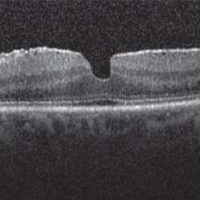

MACULAR HOLE

The macula is a small area in the center of the retina where light is sharply focused to produce the detailed color vision needed for tasks such as reading and driving. When a full-thickness defect develops in the macula, the condition is referred to as macular hole.

CAUSES

Macular hole commonly affects people over the age of 55 and most often occurs in women. The vast majority of cases develop spontaneously without an obvious cause. For this reason, there is currently no effective way to prevent their formation and development. If a macular hole develops in one eye, there is a 5% to 15% risk of one developing in the other eye.

SYMPTOMS

The most common symptom of macular hole is a gradual decline in the central (straight-ahead) vision of the affected eye. This can occur as:

• Blurring

• Distortion (straight lines appearing wavy)

• A dark spot in the central vision The degree to which vision is affected will depend on the size and location of the macular hole, as well as the stage of its development.